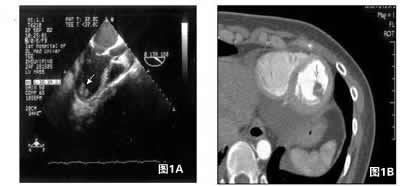

图1:超声心动图(A)及多层螺旋CT(B)均提示左心室占位(箭头所示)。

诊治经过 进行药物治疗2周后,患者呼吸困难等症状明显缓解,可以平卧及轻体力活动。但仍有心悸感,动态心电图检查仍为无休止性的心动过速。进行经食管心脏超声多平面126度左室长轴切面清楚显示左心室尖部有一团块状物,分叶,形态不规则,质地尚均一,活动,有短蒂与室壁相连(图1A)。多层螺旋CT(MSCT)显示左心室腔近心尖部见一低密度团块影,边界清楚,大小约0.8 cm×0.9 cm,密度均匀,带蒂,附着于左心室,提示左室黏液瘤的可能性大(图1B)。